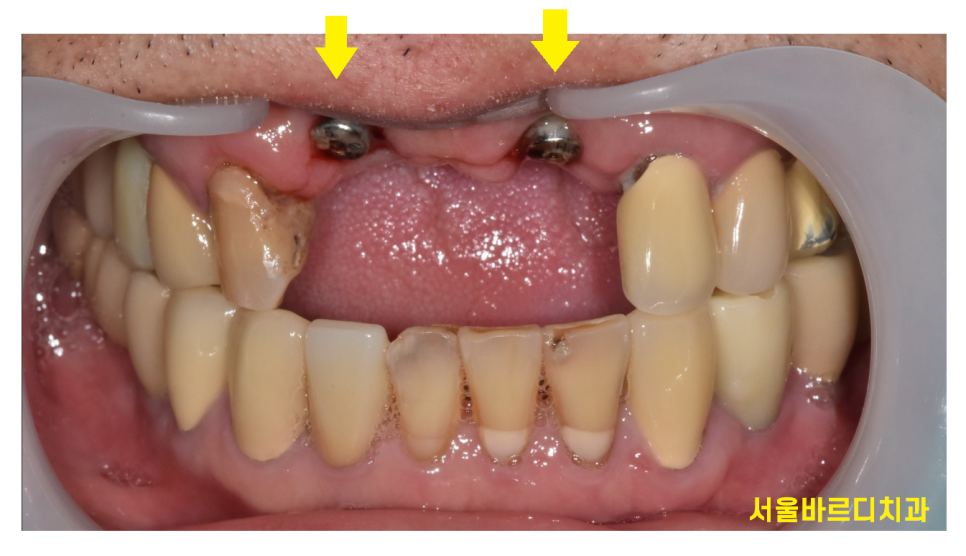

틀니를 빼면 이런 형태입니다~

너무 잘보이는 대문니라 틀니를 제작해드렸고

2달정도 지나 보철을 제작해드렸습니다.